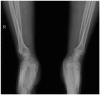

Distal radioulnar joint (DRUJ) instability is a complex condition that can severely affect forearm function, causing pain, limited range of motion, and reduced strength. This review aims to consolidate current knowledge on the diagnosis and management of DRUJ instability, emphasizing a new classification system that we propose. The review synthesizes anatomical and biomechanical factors essential for DRUJ stability, focusing on the interrelationship between the bones and surrounding soft tissues. Our methodology involved a thorough examination of recent studies, incorporating clinical assessments and advanced imaging techniques such as MRI, ultrasound, and dynamic CT. This approach allowed us to develop a classification system that categorizes DRUJ injuries into three distinct grades. This system is intended to be practical for both clinical and radiological evaluations, offering clear guidance for treatment based on injury severity. The review discusses a range of treatment options, from conservative measures like splinting and physiotherapy to surgical procedures, including arthroscopy and DRUJ arthroplasty. The proposed classification system enhances the accuracy of diagnosis and supports more effective decision making in clinical practice. In summary, our findings suggest that the integration of advanced imaging techniques with minimally invasive surgical interventions can lead to better outcomes for patients. This review serves as a valuable resource for clinicians, providing a structured approach to managing DRUJ instability and improving patient care through the implementation of our new classification system.